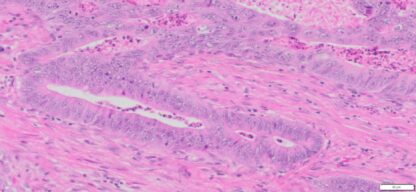

| HumanRectum | Moderately differentiated adenocarcinoma of the Rectuma | Female/59 | 45% | II | pT3pN1bpMx | MLH-1,MSH-2,MSH-6 and PMS-2: Preserved nuclear Staining |

Images for H&E Stain and IHC